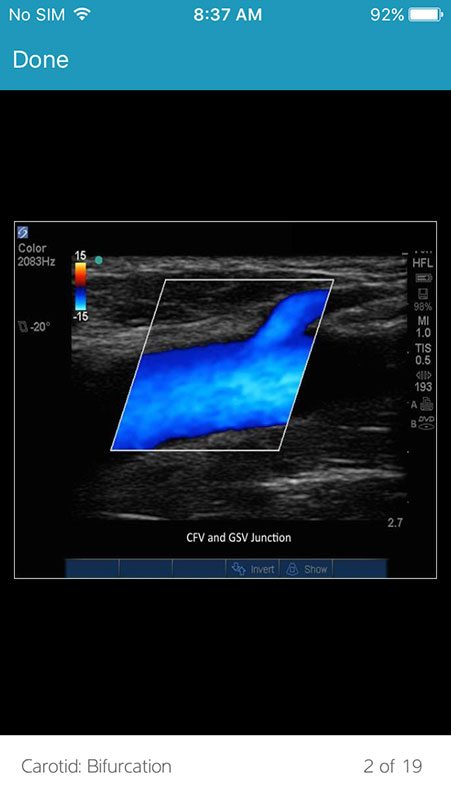

Some videos use 3D anatomic models side-by-side with real-time ultrasound images to demonstrate a technique. Videos are usually taught by an instructor, explaining the transducer orientation alongside the ultrasound images.

The videos also include annotations for important anatomic structures, as well as narration that describes each technique.

The Images section contains still images of ultrasound scans showing different anatomic systems, with or without labels. Images have no textual descriptions or narration tho.